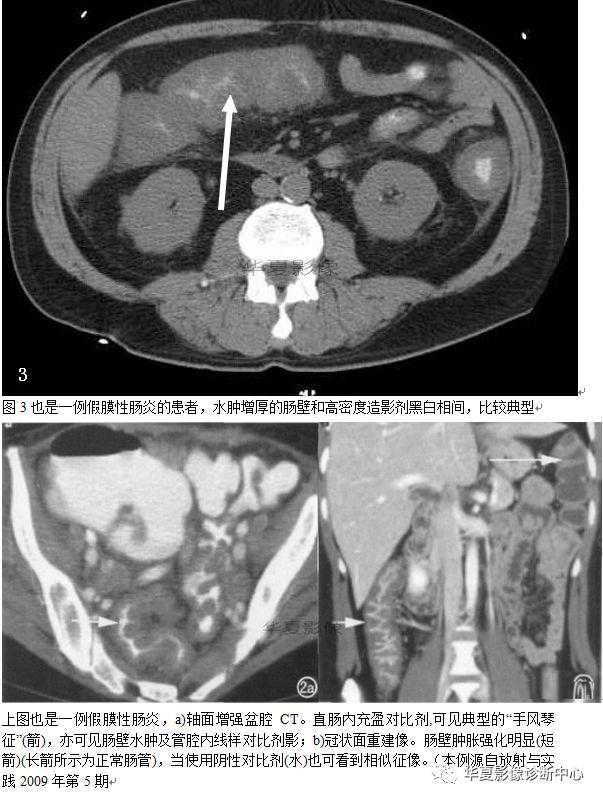

036:手风琴征:

手风琴征见于口服对比剂后腹部CT扫描,主要指大肠内由低密度的软组织影与高密度的对比剂相交互而形成手风琴样的表现。手风琴征中低密度的软组织影代表了由于肠壁水肿引起显著增厚的结肠皱襞,口服对比剂后到达结肠的少量的对比剂填充于增厚的结肠皱甓之间的裂隙内,这种低密度与高密度相间的条带状表现与手风琴非常相似。根据结肠水肿的程度不同以及对比剂在结肠皱襞的裂隙间沉积量的多少而表现有所不同。该征被认为是假膜性结肠炎(PMC)的特征性CT表现。

PMC的致病机制主要是结肠内难辨棱菌,或称艰难棱菌、顽固性梭状芽胞杆菌的过度生长,这是由于抗生素大量使用而引起肠道内正常菌群减少的一种反应,某些抗肿瘤药也可以产生同样的作用。难辨梭菌是革兰阳性厌氧菌,这些细菌所产生的毒素能够直接引起肠黏膜的损伤。其特征性的病理改变是在病变的结肠黏膜表面附着有不连续的、小的黄色斑块(假膜),少数情况下可累及小肠。假膜是由一层坏死的上皮细胞碎屑、纤维、多形核白细胞以及黏液共同组成。影像检查并不能直接分辨这些假膜斑块。随着疾病的进展,炎性水肿可逐渐累及黏膜固有层、黏膜下层.最终到达浆膜下,导致肠壁全层水肿增厚,这个病理改变可以在影像学上表现出来。普通X线检查能够发现一些非特异性的表现如结肠皱襞的增厚、结肠的扩张,腹腔积液等。CT检查越来越多地心用于那些没有特异性症状的、难以诊断的进展性PMC患者,其CT表现与普通X线相类似,包括肠壁的明显增厚、肠壁结节、手风琴征。肠壁增厚和结节的出现也可以见于其他的结肠炎,但主要是在PMC的患者身上有所体现,其肠壁增厚的程度和结节的出现才能够在CT上表现为手风琴征。研究认为,进展期PMC患者CT检查发现手风琴征的阳性率占51%—67%.有学者认为它是PMC的特征性表现。

PMC的确诊依靠粪便的毒素检查阳性和结肠内镜下对可见假膜斑块的检出。当然需要我们已经预料到了该病的可能性。不然则不会在早期进行这些检查。而且粪便毒素检测需要两天才能出结果,结肠镜检也可能出现假阴性或特异性的结果。所以影像学检查或许是较早发现该病的检查手段。PMC可以治愈,但如果治疗不及时则可能危及生命。因此及时诊断并予以治疗意义重大。